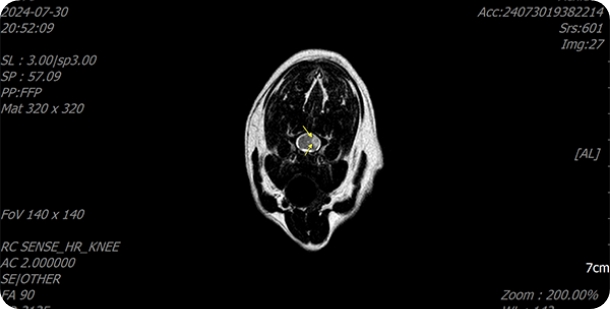

MRI 검사

영상전공의 수의사가 검사를 직접 진행하며

최신 호흡 마취 시스템과

마취 전담팀과 함께

안전하게 운용하고있습니다.